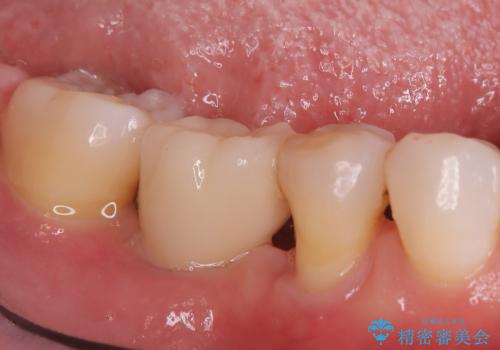

右下6番のインプラント治療: 5番の歯周組織が安定し、7番の傾きが改善された後、失われた6番の部分にインプラントを埋入。周囲の歯と調和した被せ物を装着し、強固で自然な奥歯を再建しました。

この総合的な治療により、右下奥歯全体の歯周環境と咬み合わせが劇的に改善。患者様には、安定した咬み心地と、将来にわたって歯を長持ちさせる環境を獲得していただけました。